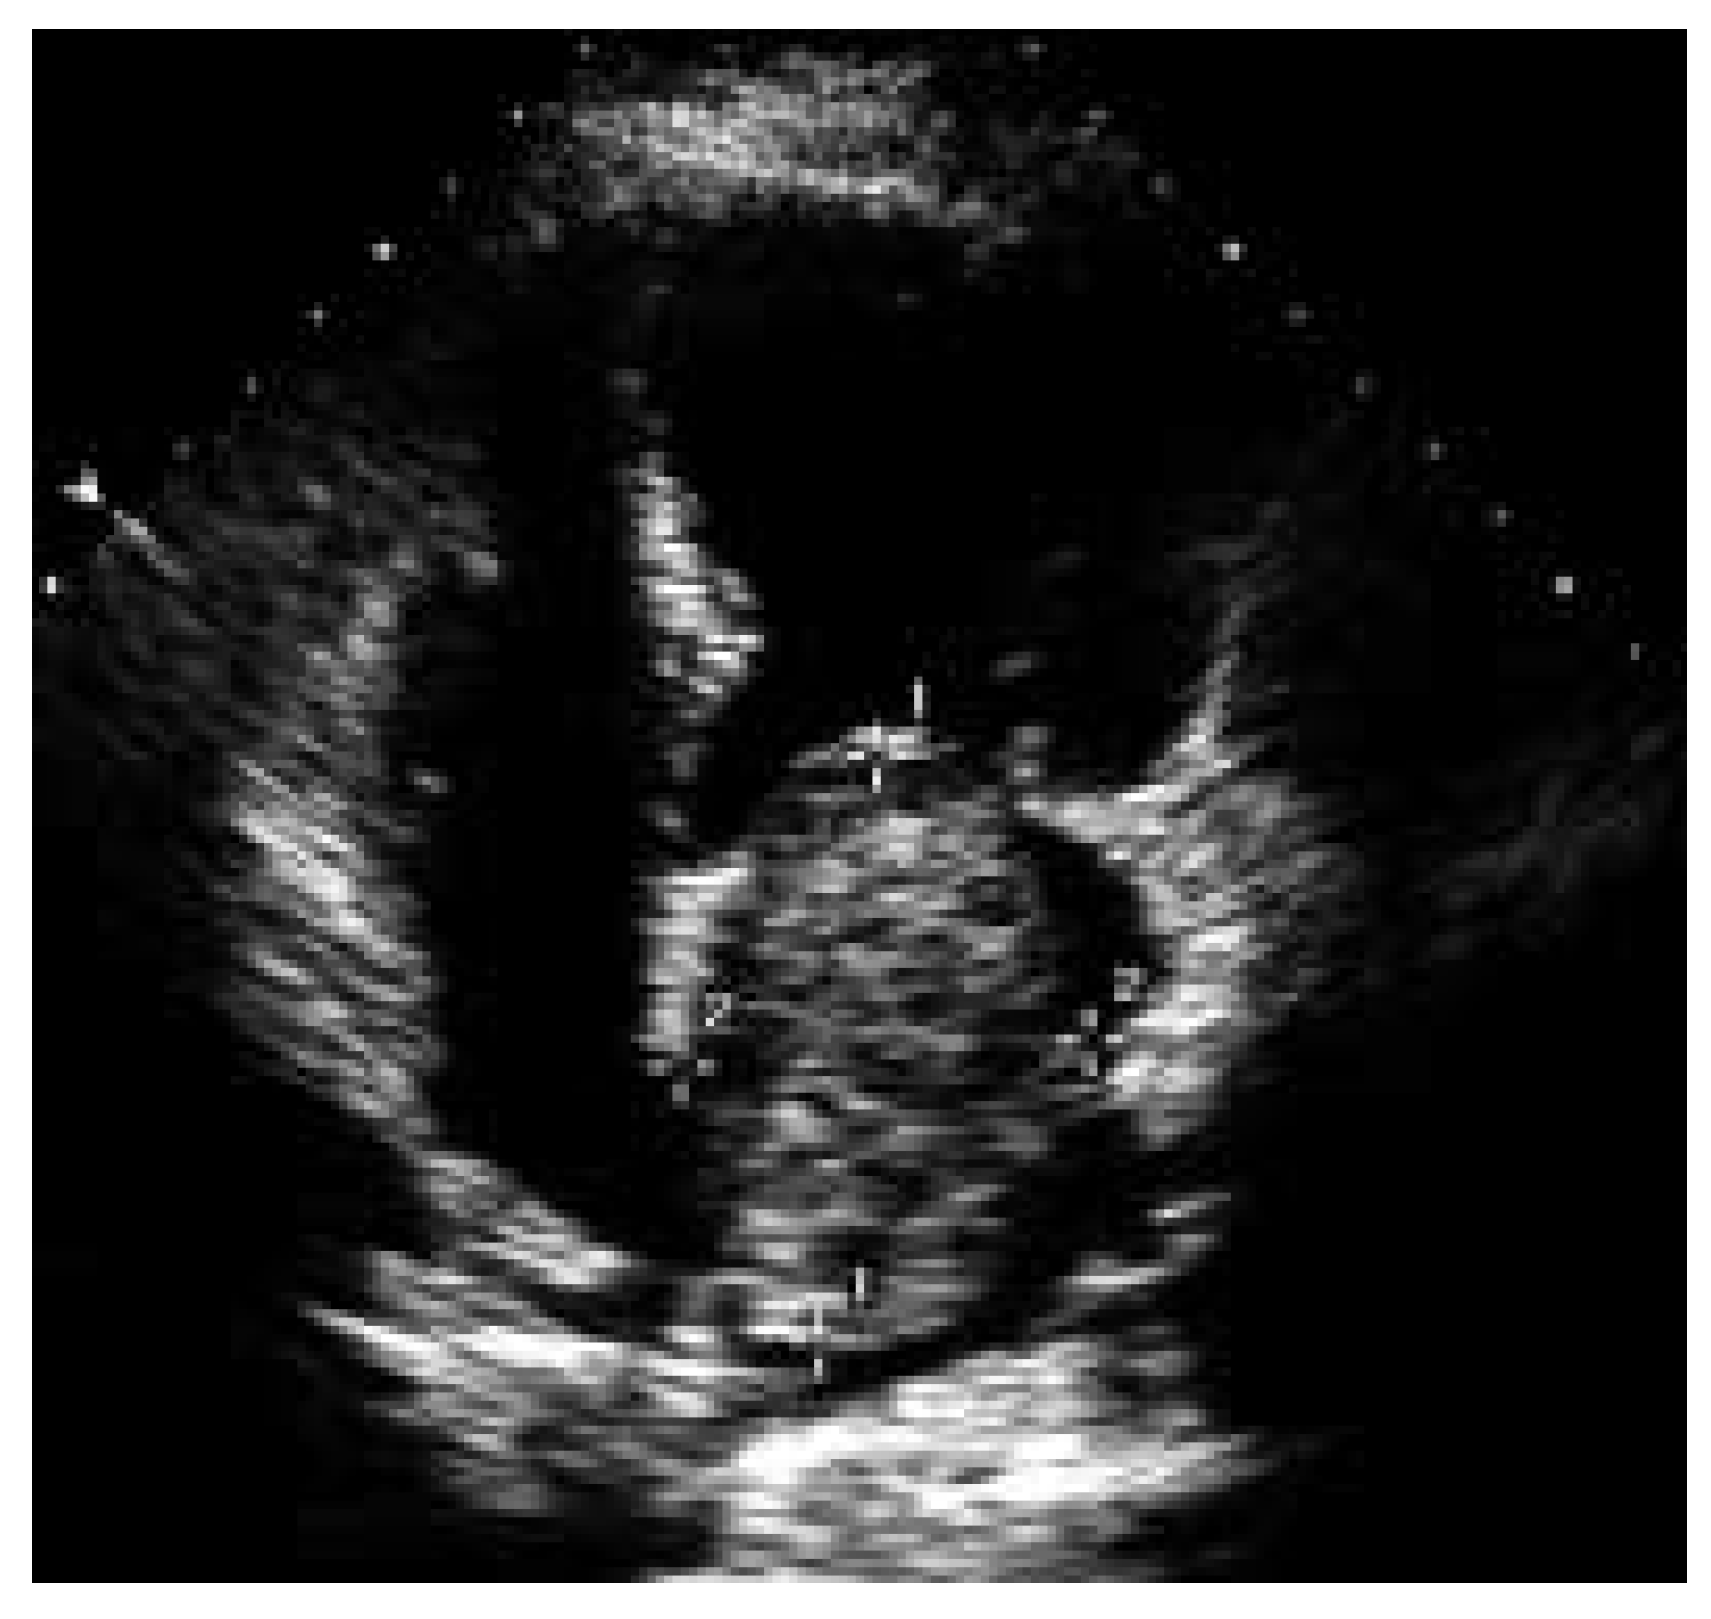

An echocardiographic example of large myxoma in a 57-year-old patient in whom only minor elevations of CRP and IL-6 levels were present is shown in Figure 3.

Figure 3. Example of a large myxoma with only minor elevations in IL-6 and CRP levels. This is the example of a large myxoma (125 mL) in a 57-year-old female with only minor elevations in CRP levels (11.1 mg/l; normal <5) and IL-6 levels (5.1 pg/mL; normal <3.1).